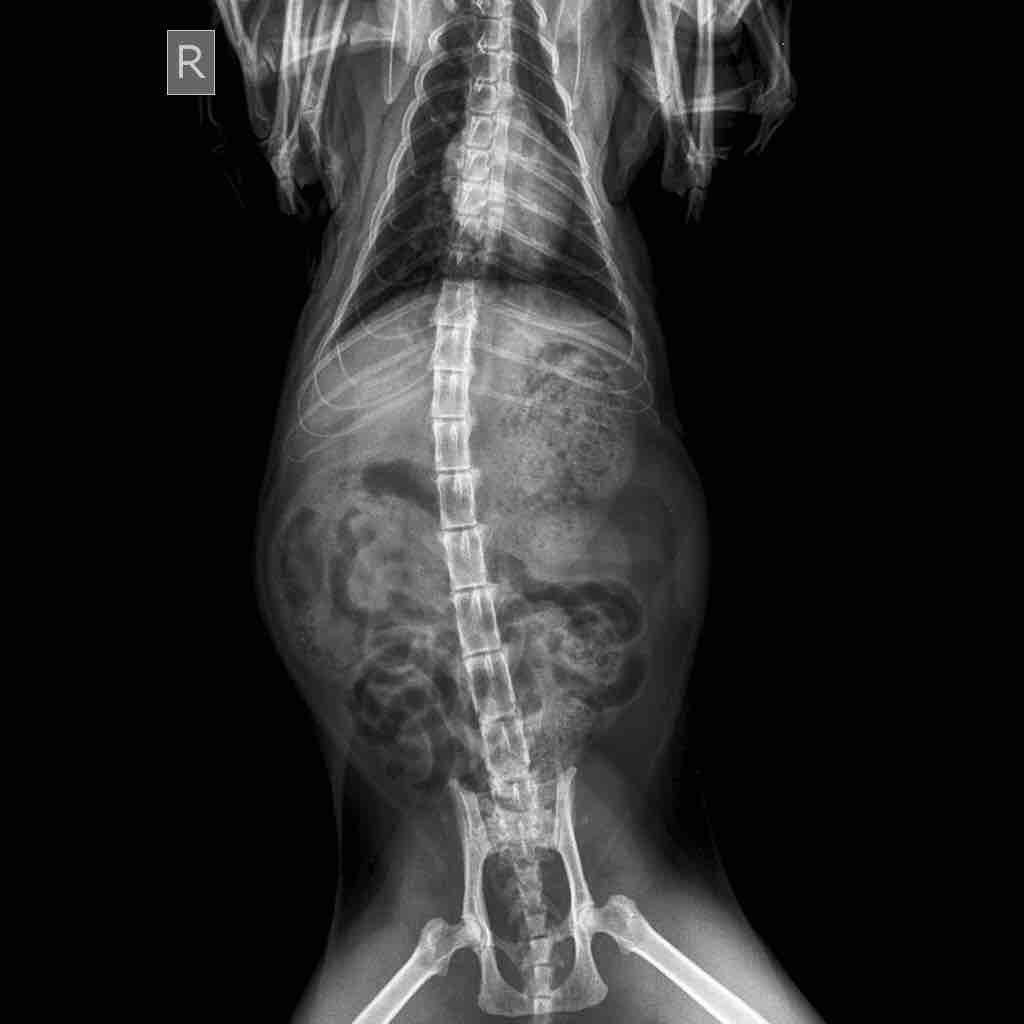

I got an abdominal x ray of my cat today. Looking at it, my vet said that her bladder is full of stones. But after comparing the x Ray to those online, I don’t see them. Could you please take a look at these x rays and tell me if there are crystals or stones present? Thank you very much

The back legs are tucked up over the bladder, so it is hard to say for certain, but I do not see any large stones in the urinary bladder. I would need to spin down a sample of urine and look at it under a microscope to see if there are urinary crystals since those do not show up on x-rays.